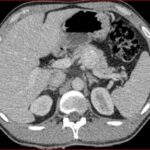

Caso 2

Paciente femenina de 48 años de edad que ingresa a Hospital Sanatorio Franchin por síntomas de cefalea y mareos, cuadro que se hace progresivo, presentando síncopes y posteriormente alteración del estado de conciencia. Los exámenes clínicos revelan una glucosa de 40 mg/dl, concomitante con insulina alta y péptido C elevado. Ingresa de forma programada para realización de duodeno pancreatectomía el 29 de mayo de 2021. Imágenes diagnósticas muestran estudio trifásico de tomografía de abdomen, lesión nodular en la cabeza del páncreas con ávido realce en fase arterial que en resonancia magnética se observa hiperintensa en T2, presenta restricción con la difusión y caída de la señal en el ADC. Además presenta realce tras la administración de contraste con gadolinio.

Estudio histopatológico reveló tumor neuroendocrino bien diferenciado grado 1.

Ahora bien, como se mencionaba al principio, el estudio ecográfico es de muy baja sensibilidad y se identifique o no la lesión por este estudio, nuestro siguiente paso en el algoritmo diagnóstico de esta lesión es la tomografía. Esta es la prueba no invasiva inicial, con una sensibilidad del 63% al 83%, y detecta del 70% al 80% de los tumores. Esta debe realizarse como un estudio trifásico: fase arterial temprana a los 30 segundos, fase venosa a los 70 segundos, fase tardía de 3 a 5 minutos. La característica de estos tumores por tomografía es que se presentan como una masa sólida que tiene un ávido realce en la fase arterial, cuyo realce se mantiene y se observa más tenue en la fase venosa y en los tiempos tardíos la lesión se homogeniza.

La resonancia magnética es el otro estudio de imagen no invasivo que nos permite la detección de la lesión con una sensibilidad mayor que la de la tomografía, del 85% al 95%, donde los insulinomas presentan un realce tras la administración de contraste con gadolinio y secuencias T1 sin contraste son lesiones hipointensas y en secuencias T2 son hiperintensas.

Para mi caso, y dando una visión general de los métodos de imagen no invasivos en esta revisión retrospectiva, solo a uno de los pacientes se le detectó la lesión por ecografía, donde se visualizó una lesión nodular hipoecogénica en el cuerpo del páncreas. A los demás pacientes se les detectó la lesión por tomografía en estudio trifásico, donde resaltan las características ya descritas por la literatura de lesiones hipervasculares con intenso realce en fase arterial, localizadas en diferentes partes del páncreas, como cabeza, cuerpo y cola.

La resonancia magnética confirmó aún más el diagnóstico de las lesiones ya previamente visualizadas en tomografía en esta revisión, con realce de las lesiones en secuencias T1 y contraste con gadolinio, y en las secuencias funcionales con restricción de la lesión y caída de la señal en el mapa de ADC.